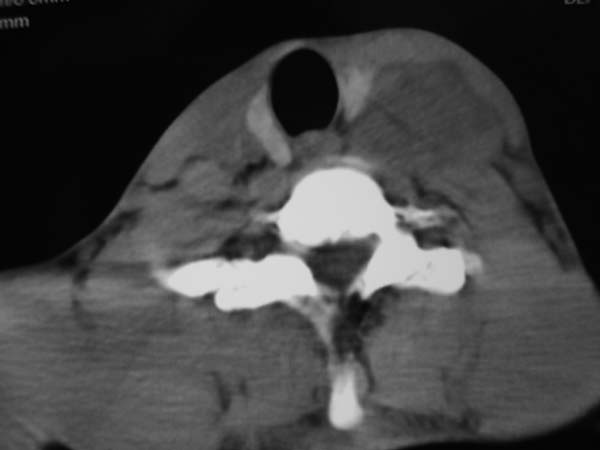

标题: CT7516[颌面颈部]:颈部病变,请会诊!

患者男性,37岁,农民,自觉左颈部肿大三天,无其它不适。

左侧颈部软组织密度肿块,界限清楚,形态不规则,占位效应明显。考虑:1 淋巴瘤。2 神经源性肿瘤不除外。

左颈部占位,病灶沿间隙分布,密度混浊,结合病史肿大三天,考虑1,炎症病变,建议增强。2,颈部血管性病变。

同甲状腺间有脂肪间隙存在,考虑不是来源于甲状腺,肿大淋巴结?

左侧甲状腺在那? 病变来自甲状腺吧,甲状腺肿或腺瘤

病灶边界较清,密度不均,其内可见坏死灶,左侧甲状腺受压,考虑神经源性肿瘤可能性大,建议穿刺活检。